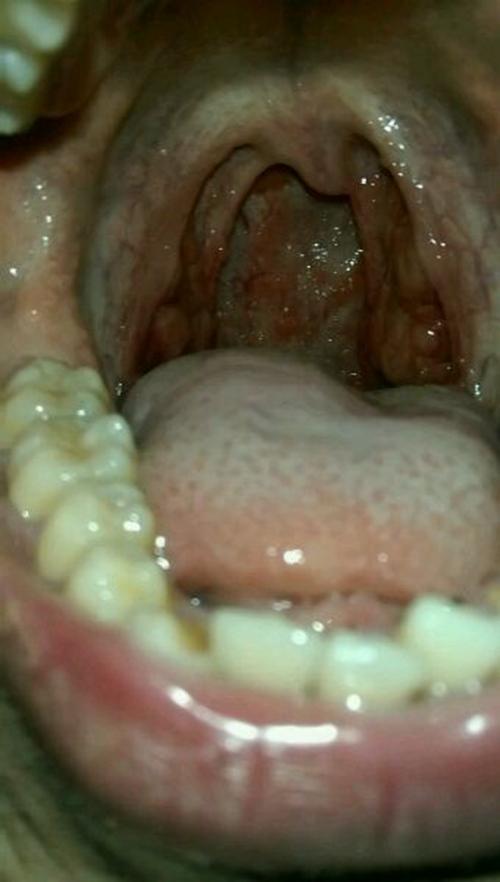

扁桃体恶性淋巴瘤图片

扁桃体恶性淋巴瘤图片,扁桃体淋巴瘤图片

扁桃体恶性肿瘤包括鳞癌,淋巴肉瘤,等恶性肿瘤,以 鳞癌较多见,癌多